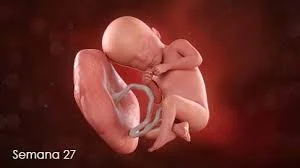

• Semana 27

Semana 27

El feto mide unos 25 cm y pesa cerca de 900 gramos. Los pulmones continúan su desarrollo, y el feto comienza a practicar la respiración de manera más regular. Su cerebro sigue desarrollándose, y su capacidad para dormir y despertar se establece más claramente. El feto puede sentir dolor y tiene mayor percepción sensorial.